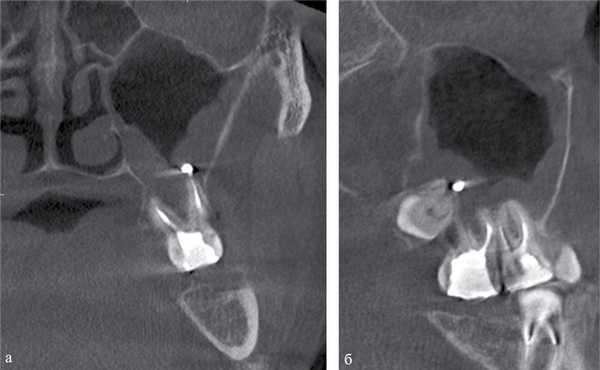

Воспалительные изменения слизистой оболочки верхнечелюстной пазухи, существующие в течение длительного времени, вовлекают в процесс костную стенку. На компьютерных томограммах отмечается утолщение костной стенки в костном режиме и появление «оптического эффекта» — уплотнение стенки в 1,5—3 раза за счет отека надкостницы — при просмотре в мягкотканом режиме (рис. 1, а, б) [9]. При одностороннем процессе, характерном для одонтогенного поражения, на контралатеральной интактной стороне такого эффекта не определяется.

Рис. 1. Рентгеновская компьютерная томограмма околоносовых пазух. Коронарная проекция: мягкотканное окно (а) и костное окно (б).

В костном режиме программы просмотра изображений утолщение костных стенок верхнечелюстной пазухи определялось в 21% случаев (рис. 2, 3), что указывает на хронический характер воспаления. «Оптический эффект» в мягкотканном режиме программы просмотра диагностических изображений определялся у 30,7% больных, что указывает на вовлечение надкостницы.